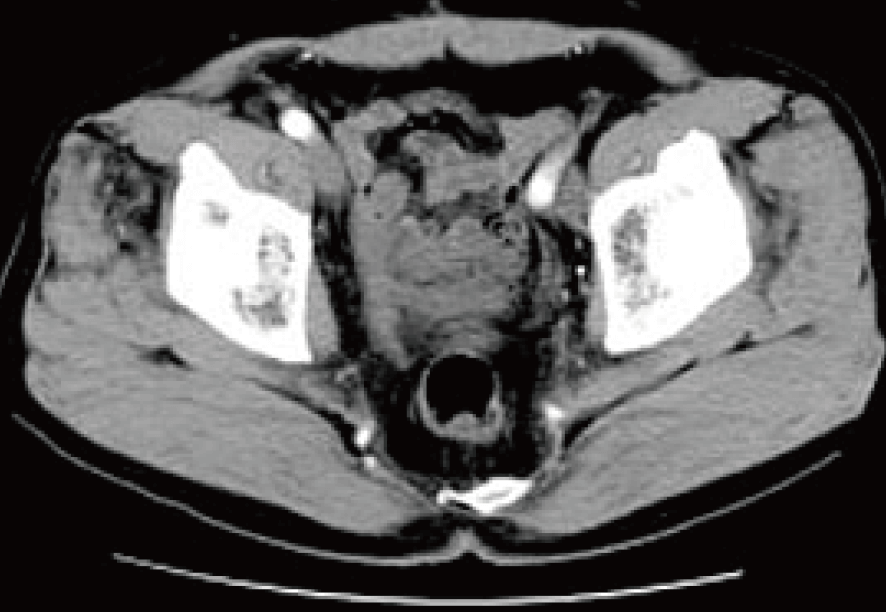

提示した下腹部CT写真は治療終了後およそ3カ月経過時点のもの。

治療前に存在していた骨盤内のリンパ節転移もほぼ消滅していた。